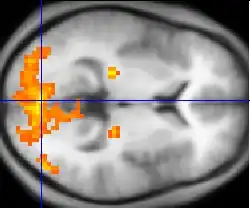

Neben der Messung und Analyse der elektrischen Gehirnaktivität können bildgebende Verfahren zum Einsatz kommen wie der PET-Scan und die funktionelle Magnetresonanztomografie (fMRT), die Einblicke in das arbeitende Gehirn und damit speziell in die Sprachverarbeitungsprozesse geben.[31]

Entscheidende Fortschritte machte die Neurolinguistik seit den 1990er Jahren mit der Etablierung neuer Technologien zur Messung und Darstellung der Vorgänge im Gehirn. Mit Elektroenzephalographie und funktionaler Magnetresonanztomografie war es möglich, das Gehirn von geschädigten und gesunden Menschen im Detail zu untersuchen. Man konnte genauere Aussagen machen, wie gesunde Menschen Sprache verarbeiten und wie ein geschädigtes Gehirn die Schäden kompensiert.[15]